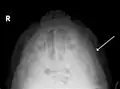

- Fracture of the zygomatic arch as seen on plain X-ray